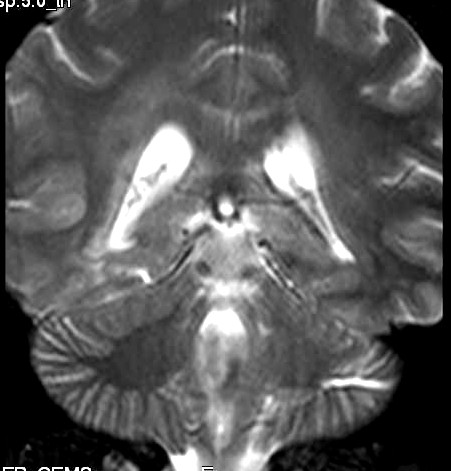

| Fem. 17a. |

| Nódulo sólido homogêneo preenchendo o III ventrículo, com limites precisos, com hipossinal em T1 e hipersinal em T2 e FLAIR, que se impregna por contraste paramagnético. Lesão menor implantada no assoalho do IV ventrículo provavelmente representa disseminação por via liquórica. |

| F. 17a. Tumor teratóide rabdóide atípico de III ventrículo. RM | HE | VIM, GFAP | HHF35, desmina, 1A4 | AE1AE3, EMA |